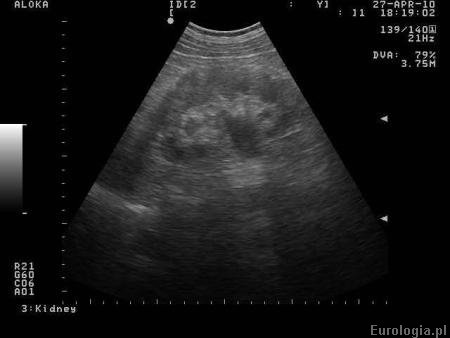

Fot. Prawostronne wodonercze u pacjentki w 29 tygodniu ciąży.

Diagnostyka przyczyn wodonercza u kobiety ciężarnej jest mocno ograniczona ze względu na potencjalną szkodliwość dla rozwoju płodu. U pacjentki w ciąży nie dąży się do ustalenia przyczyny wodonercza tylko ocenia się czy wymaga ono odbarczenia. Najczęstszą przyczyną wodonercza u ciężarnych jest wpływ progesteronu na mięśniówkę moczowodów oraz ucisk na moczowody przez powiększającą się macicę z płodem. Kolejną co do częstości przyczyną wodonercza u ciężarnych jest kamica moczowodowa i zwężenie połączenia miedniczkowo - moczowodowego. W razie konieczności wodonercze odbarcza się zakładając cewnik DJ lu nefrostomię.